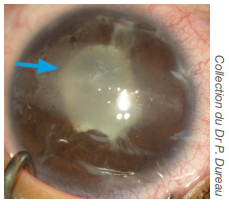

• Lésions de la cornée par dépôt de résidus calciques dans la cornée, appelées kératites en bandelettes.

Kératite en bandelettes